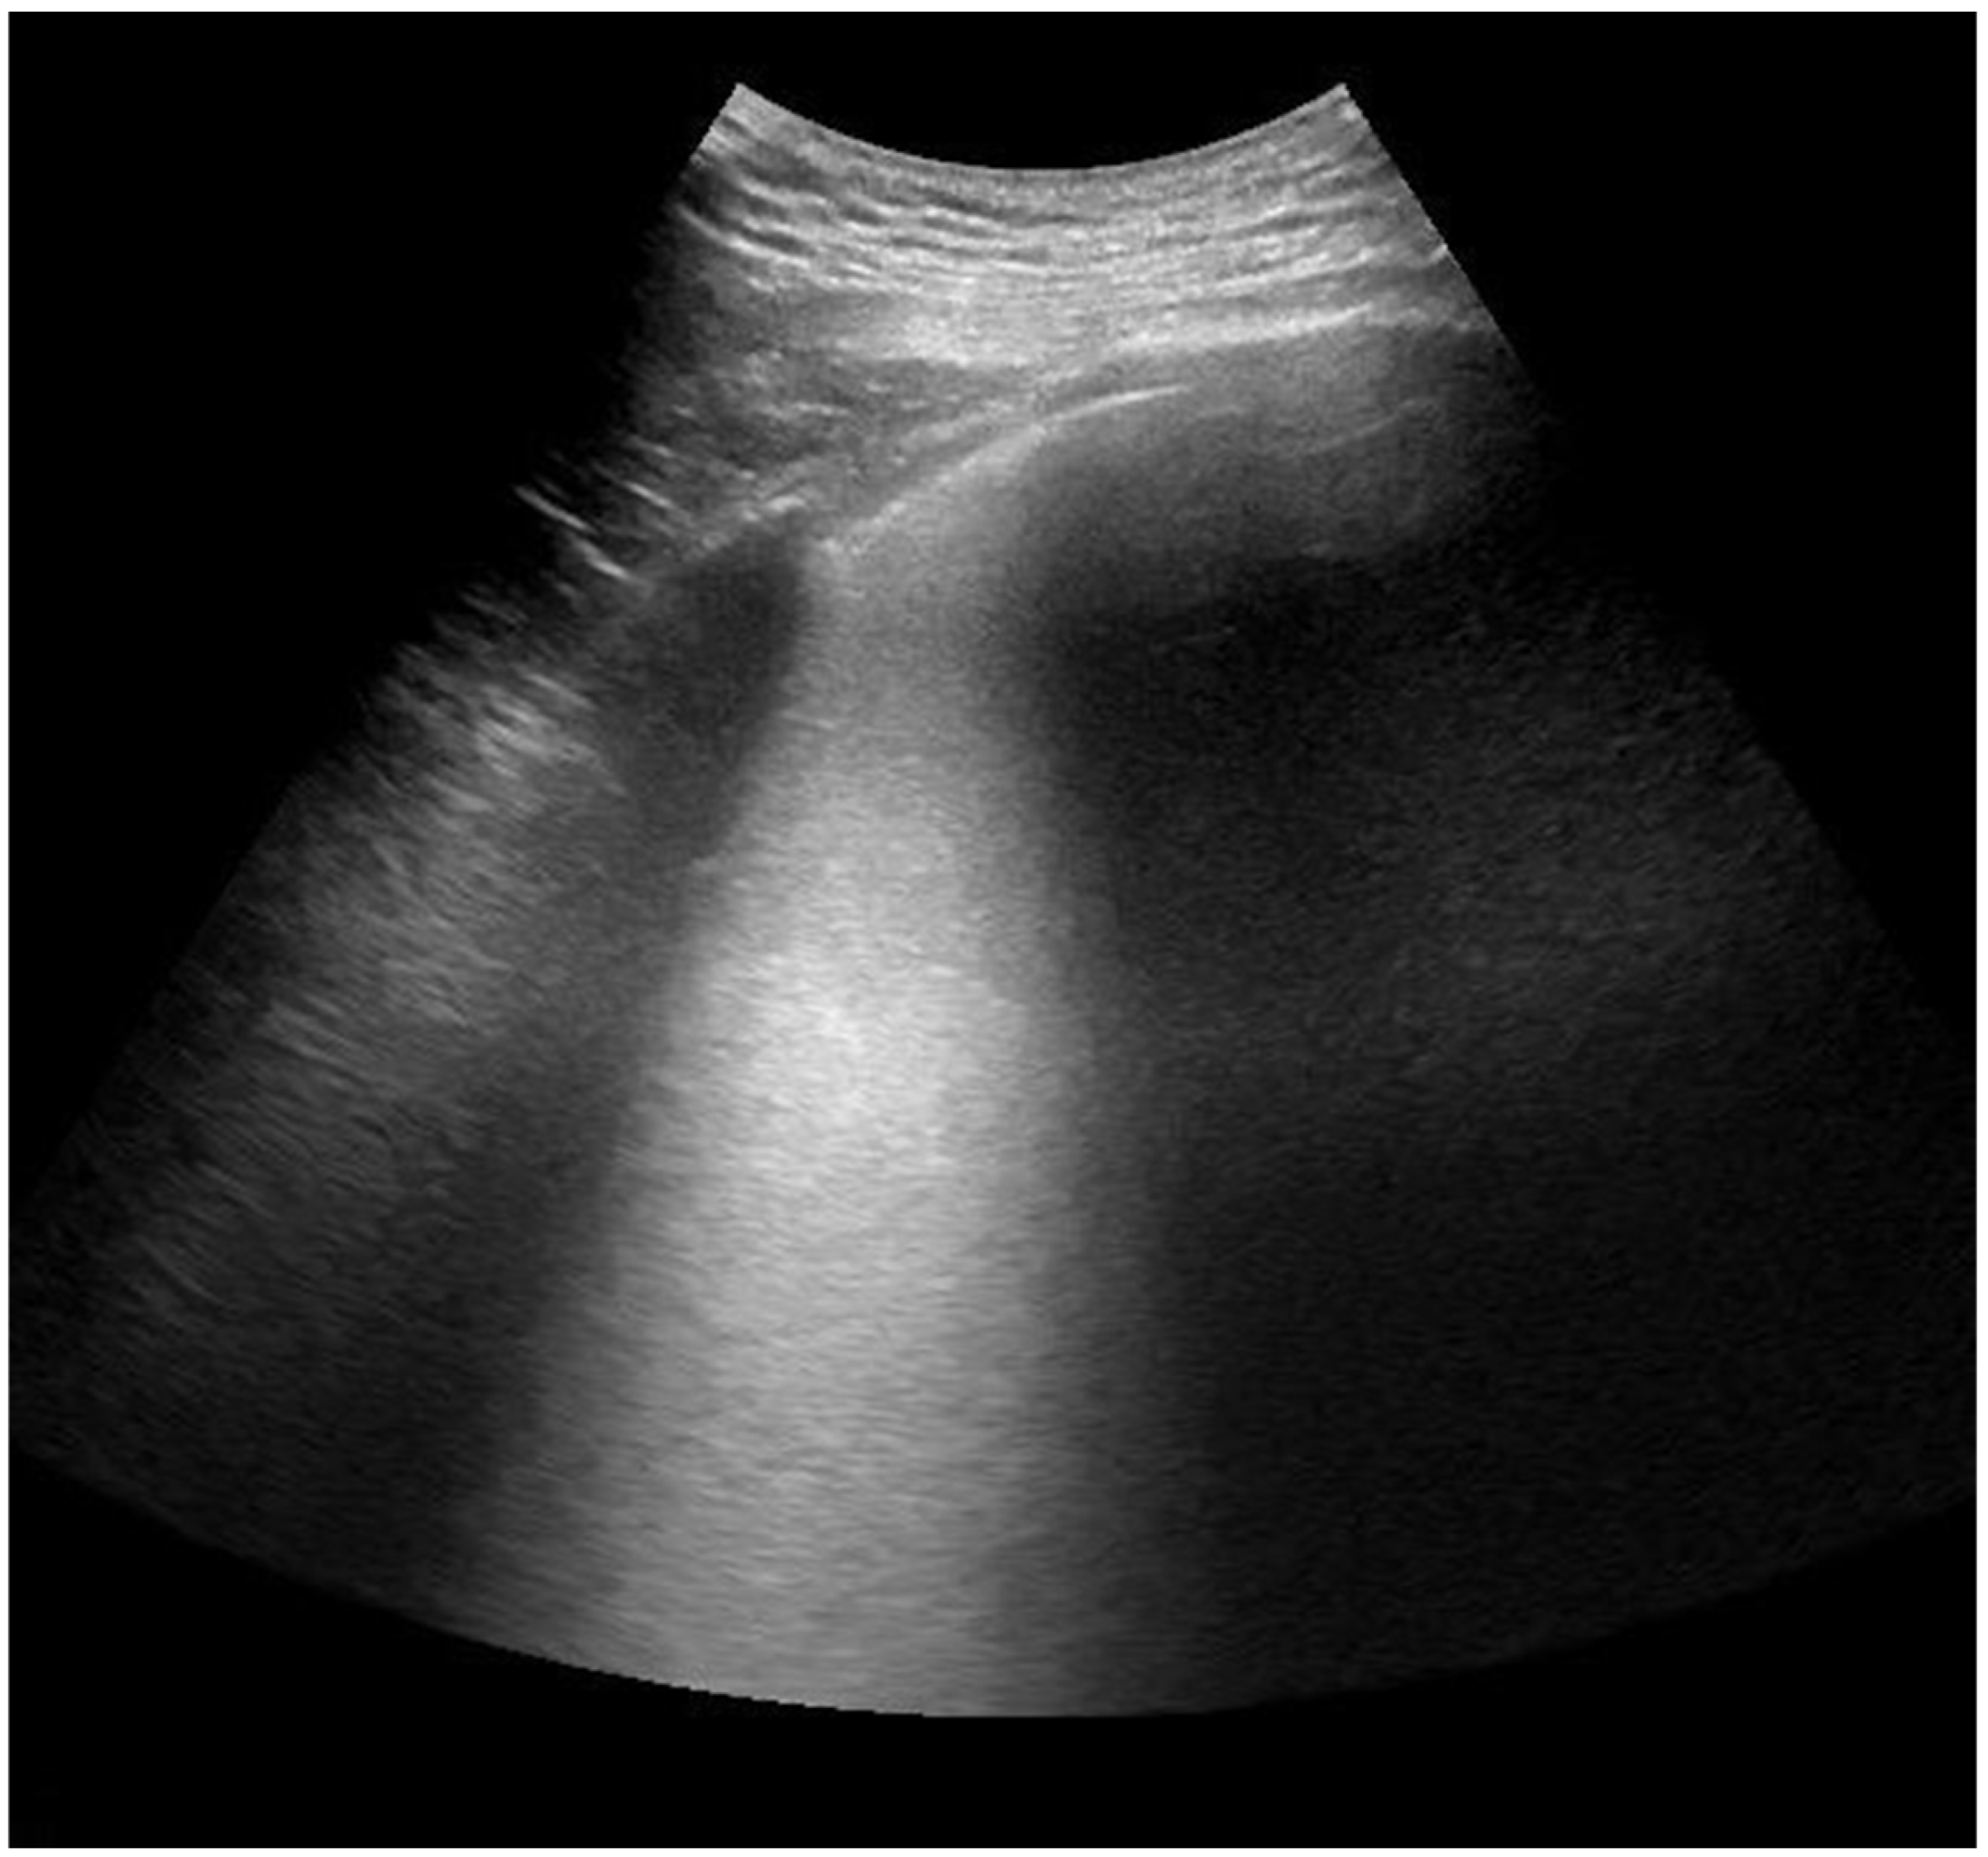

2.4. Lung Ultrasonography and Score Assessment

Appendix A

| Consolidation (C) | 11 (29%) | 4 (11%) |